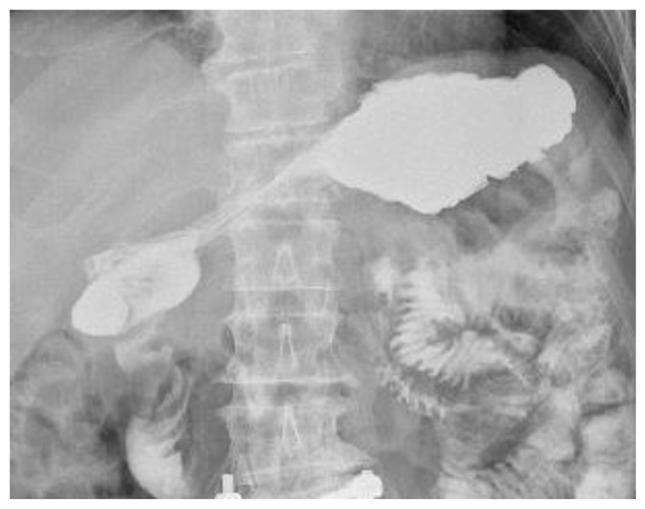

Coccidioides is a fungus endemic to the Southwestern United States, known for causing Valley Fever. While typically asymptomatic or presenting as a respiratory tract infection, rare cases of disseminated infection to the peritoneum have been reported. The patient in this case study presented with a small bowel obstruction, requiring an exploratory laparoscopy showing evidence of an inflammatory mass with a jejuna-colic fistula with adherence to the spleen. The patient underwent splenectomy with a cholecystectomy and small bowel resection. Intraabdominal cultures revealed Coccidioides, and so he started long-term antifungal treatment. The patient was also initiated on salvage chemotherapy for DLBCL, and ultimately received CAR T-Cell therapy at a tertiary center. This case report highlights a unique presentation of gastrointestinal Coccidioides infection, in the setting of an immunocompromised host with a hematologic malignancy. It also provides insight into the therapeutic challenges clinicians face when treating complicated patients such as this who require urgent chemotherapy while risking further immunosuppression in the setting of active infection.

球孢子菌是一种美国西南部特有的真菌,以引起山谷热而闻名。虽然通常无症状或表现为呼吸道感染,但也有罕见的播散至腹膜感染的病例报道。本病例研究中的患者表现为小肠梗阻,需要进行 exploratory laparoscopy(此处可能有误,推测为“ exploratory laparotomy”即剖腹探查术),结果显示有炎性肿块、空肠结肠瘘并与脾脏粘连。患者接受了脾切除术、胆囊切除术和小肠切除术。腹腔内培养发现了球孢子菌,因此他开始接受长期抗真菌治疗。该患者还开始接受弥漫性大 B 细胞淋巴瘤(DLBCL)的挽救性化疗,最终在一家三级中心接受了嵌合抗原受体 T 细胞(CAR T-Cell)治疗。本病例报告强调了在免疫功能低下且患有血液系统恶性肿瘤的宿主中,胃肠道球孢子菌感染的独特表现。它还揭示了临床医生在治疗此类复杂患者时所面临的治疗挑战,这些患者需要紧急化疗,同时在有活动性感染的情况下又有进一步免疫抑制的风险。